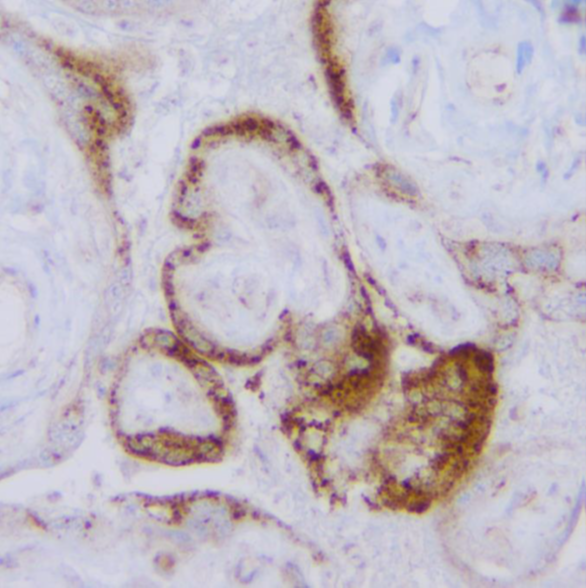

Positive control: infected lung, placenta

Application IHC